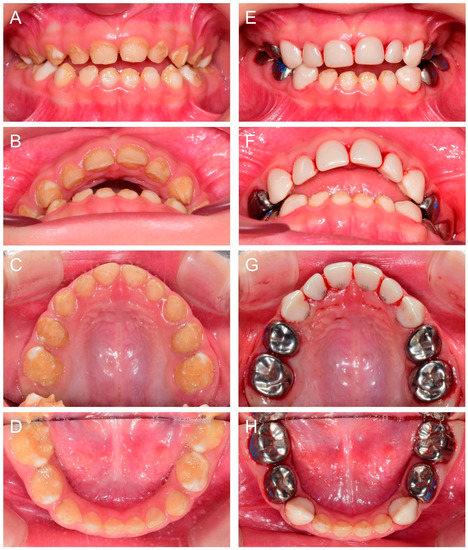

Another cousin (IV:2) of the proband, a younger brother of the affected individual (IV:1), presented for the same reason at age 1Y2M. The same treatment strategy was planned, and full-mouth restoration was performed at age 2Y9M. Deciduous molars and canines were treated with stainless steel crowns and all anterior teeth were treated with zirconia crowns (Figure 5).

Figure 5.

Clinical photos and panoramic radiograph of the affected individual (IV:2). (A–C) Clinical photos of the proband before the treatment at age 2 years 9 months. (D–F) Clinical photos of the proband after the treatment at age 3 years 6 months. The deciduous molars and canines were treated with stainless steel crowns and all anterior teeth were treated with zirconia crowns. (G) Panoramic radiograph at age 3 years 6 months.